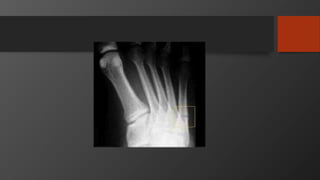

Fifth Metatarsal Fractures

• Common injury

• Divided into 3 zones

• Zone 2 is Jones fracture

• Zone 1 is Pseudojones fracture